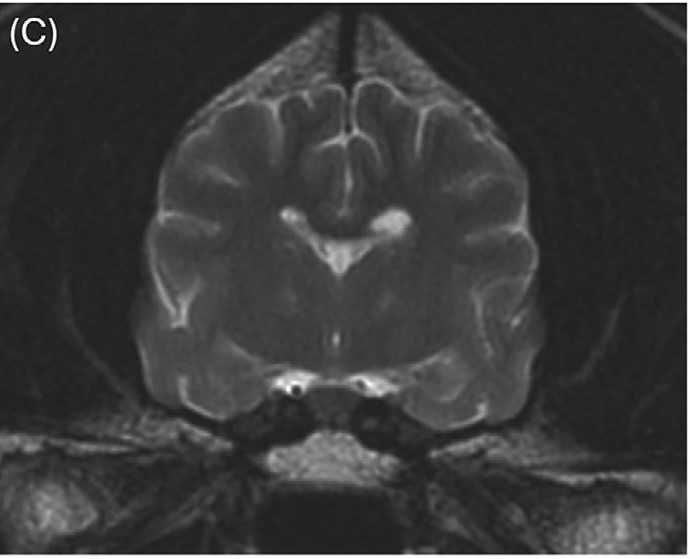

与治疗前相比,先前注意到的T2和T2-FLAIR高信号区域都有显著改善。在丘脑(图4C)、内侧和外侧膝状体以及红核中仅见非常轻微的双侧对称、边界不清的T2高信号(图5C)。先前注意到的豆状核中的T1高信号区域已完全消失(图6B)。

图4.(C)铜螯合治疗开始7个月后,丘脑核的T2高信号明显改善。

图5.(C)铜螯合治疗开始7个月后,内侧和外侧膝状体区域及红核区域的T2高信号明显改善。